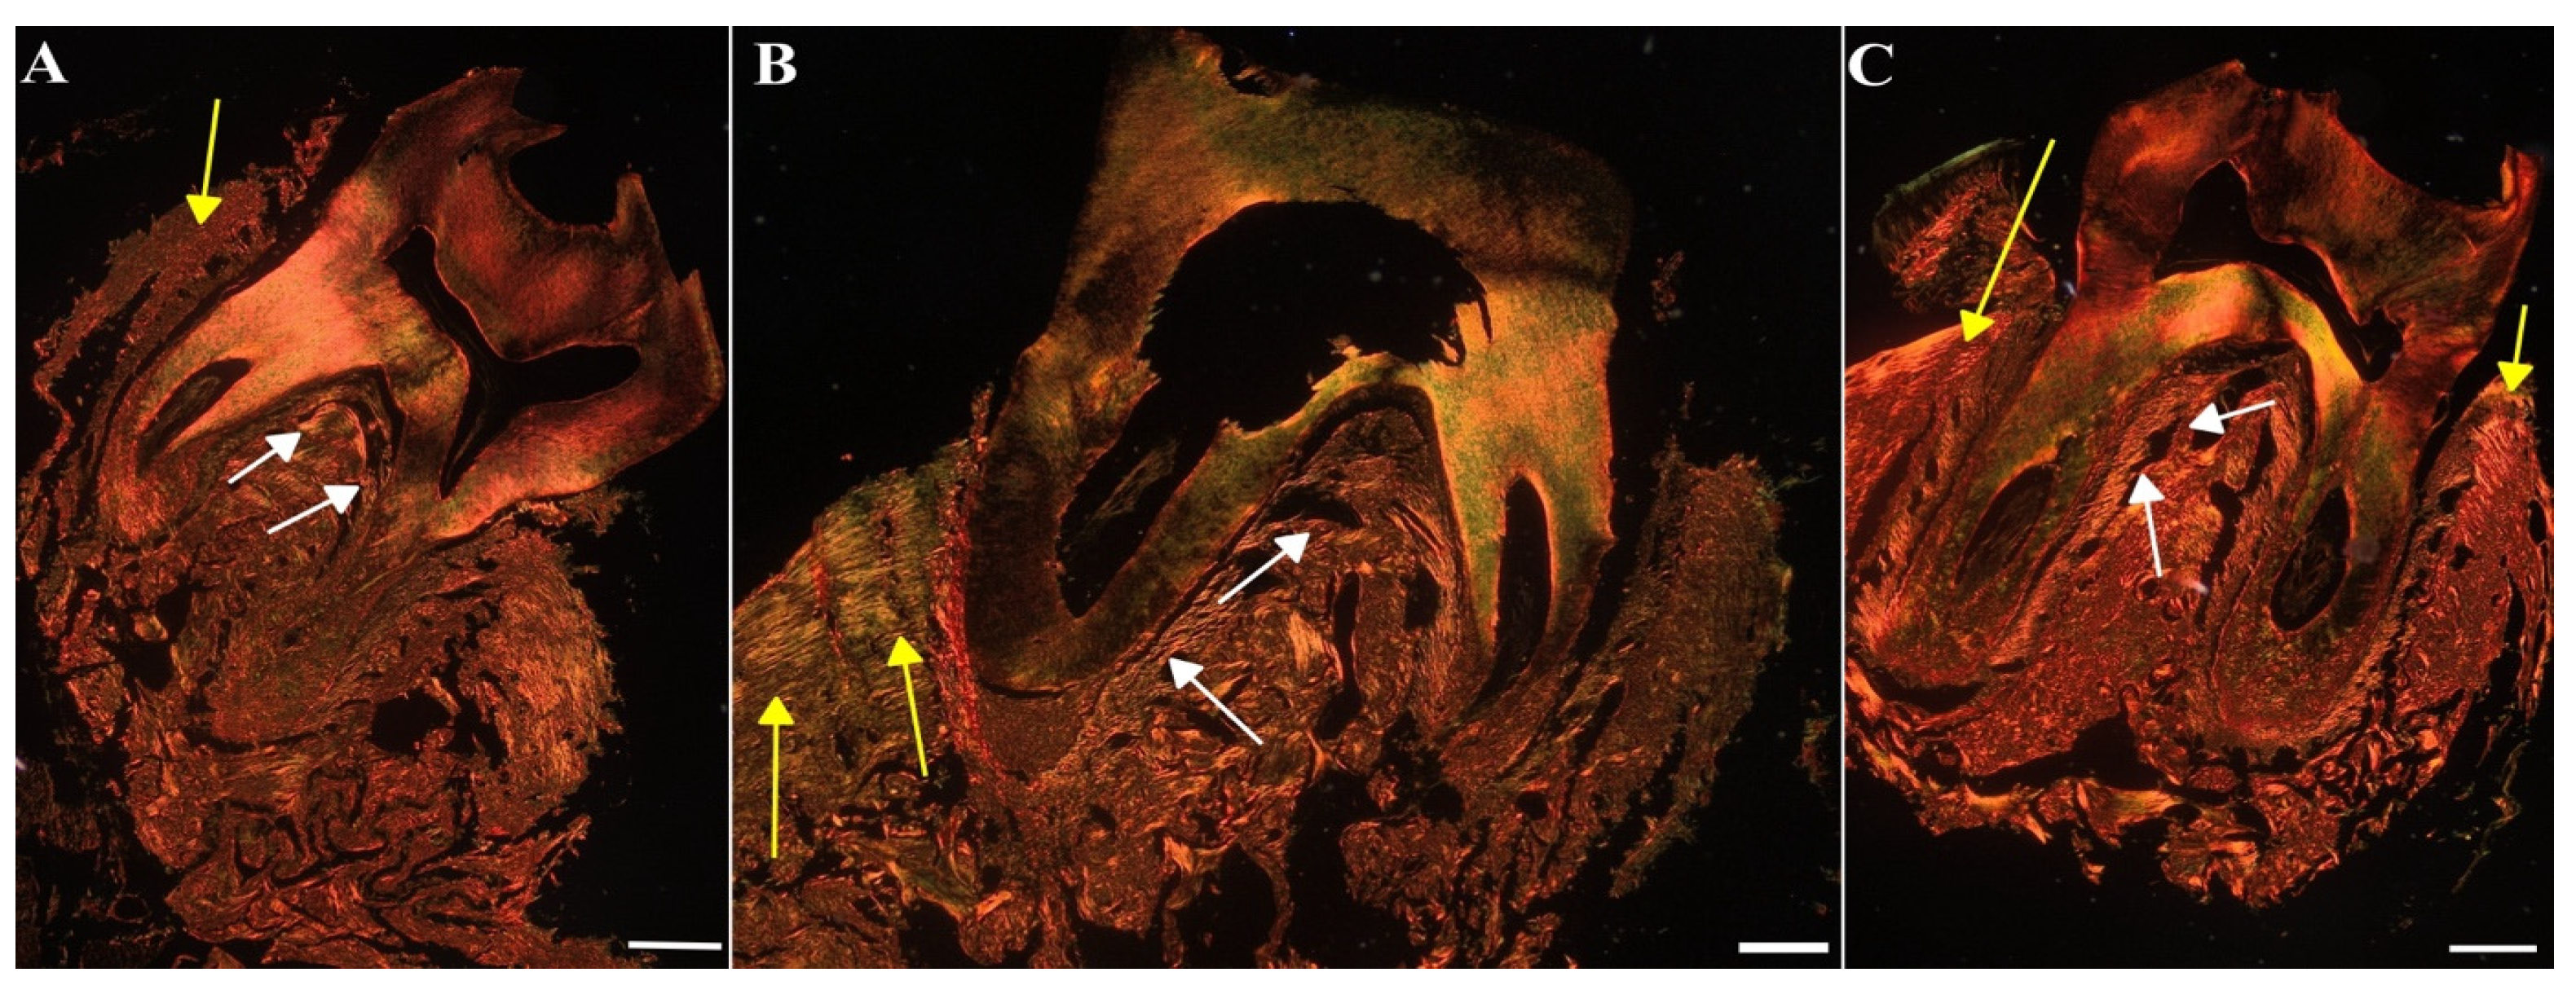

To assess the impact of MIN-T on the bone structure changes during periodontitis, immunohistochemical analysis of rat jawbone was conducted. Picrosirius red (PSR) staining was used to distinguish young and maturated collagen fibres in both compact and trabecular bone (indicated by yellow and white arrows, respectively, in Figure 11).

Another staining using toluidine blue was used to assess the microarchitecture of the trabecular bone and calculate the BV/TV parameter, which quantifies trabecular bone volume. Again, in the figure the compact and trabecular bone are clearly visible (indicated by yellow and white arrows, respectively, in Figure 12).

Significant differences (p < 0.05) were observed between the groups (Table S2): control (CG), untreated periodontitis (PG), and periodontitis pretreated with MIN-T (PG+MIN-T). Post-treatment, the trabecular bone volume (BV/TV) was slightly reduced in the treated group (PG+MIN-T), while it remained similar in both the control (CG) and untreated periodontitis (PG) groups. Additionally, there was a significant (Table S2) increase in trabecular separation (Tb.Sp) in the maxillary bone of the treated group (PG+MIN-T) compared to the control (CG) and untreated (PG) groups. This increase may indicate a potential weakening of the trabecular bone’s microarchitecture in the individuals who received the drug. Other parameters, such as trabecular number (Tb.N) and trabecular thickness (Tb.Th), showed no treatment effects on the microarchitecture of the trabecular bone (Table S2). For the trabecular bone, coarse collagen bundles were more prevalent in both the control group (CG) and the treated group (PG+MIN-T) compared to the infected, untreated group (PG) (Table S3), where bone tissue structure appeared significantly weakened. Because the Tb.Sp parameter is only one out of several indicators describing the microarchitecture of the trabecular bone and other parameters like Tb.Th and Tb.N are not affected, a significant deterioration in bone structure can be denied at this stage of investigation.

The ratio of fine-fibrous young to coarse-fibrous maturated collagen (Y/Mcompact) in the maxillary compact bone was significantly (p < 0.05) lower in the treatment group (PG+MIN-T) than in both the control (CG) and untreated (PG) groups (Table S3). This suggests that the local administration of the minocycline formulation may have induced the synthesis of new collagen. Furthermore, the proportion of maturated coarse-fibrous collagen (%Mcompact) in the compact bone of the maxilla was higher in both the treated (PG+MIN-T) and untreated (PG) groups compared to the control group (CG) (Table S3), indicating a compromised bone structure in the area due to the infection with P. gingivalis.

Interestingly, in the PG+MIN-T group, the size of the intertrabecular spaces in the maxillary bone was significantly larger, compared to the control (CG) and non-treated (PG) groups. This may suggest a potential weakening of the trabecular bone microarchitecture as a first impression. The trabecular space (Tb.Sp) parameter is thereby only one of several indicators describing the microarchitecture of the trabecular bone. If an increase in Tb.Sp would be associated with a thinning of the beads (a decrease in trabecular thickness, Tb.Th) and a decrease in the number of bone beads (Tb.N.), then this would indicate a significant deterioration in bone structure. The study results clearly show that MIN-T is not affecting other parameters, such as Tb.N and Tb.Th. Following this information, the application of MIN-T seems not to have a significant negative influence on the microarchitecture of the trabecular bone. For a complete picture, bone strength tests will be a valuable source of information. Therefore, it is planned to expand the analyses to include such techniques in future studies. Additionally, the non-treated periodontitis group PG exhibited a decrease in the percentage of maturated coarse-fibrous collagen and a significant increase in the percentage of fine-fibrous collagen as well as the ratio of young fine-fibrous to maturated coarse-fibrous collagen bundles within the trabecular bone of the maxilla, compared to both control and treated animals PG+MIN-T. This might indicate disturbances in the collagen network of the trabecular bone in the jaws of infected rats, suggesting that drug administration positively affects bone turnover by eradicating bacteria, and indicating induction of new collagen synthesis following an anti-infective treatment.

Moreover, the percentage of coarse-fibrous collagen (%Mcompact) in the compact bone of the maxilla was significantly increased in both untreated (PG) and treated (PG+MIN-T) animals compared to controls (CG), signaling a compromised bone structure in this area of the maxilla due to an infection with P. gingivalis. In summary, while the administration of MIN-T does not enhance the microarchitecture of the trabecular bone in the maxilla, it also does not significantly deteriorate it. Furthermore, drug administration does not significantly impact collagen synthesis, which could potentially increase the stability of collagen fibres and improve the condition of the trabecular bone.